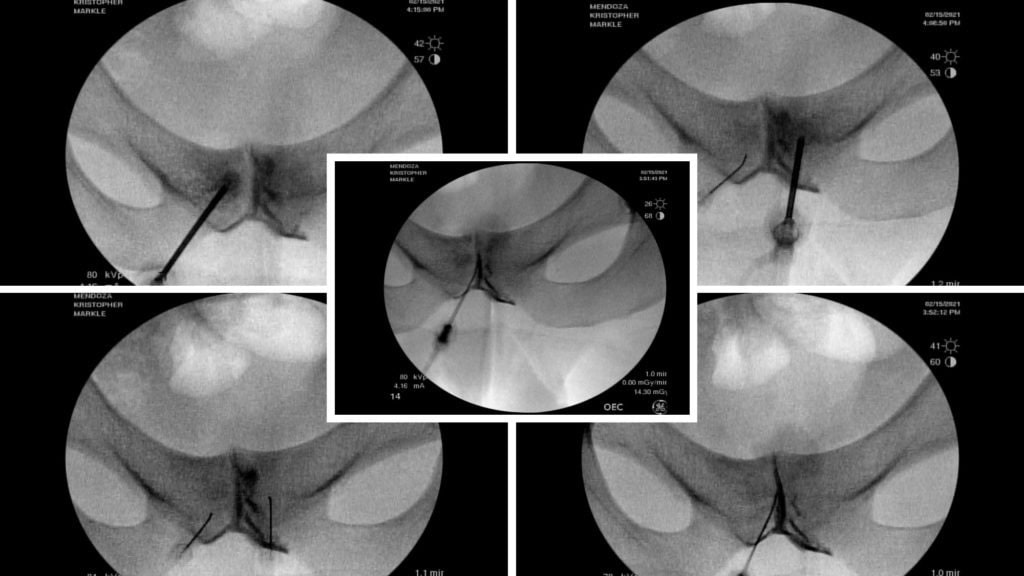

Physicians in the licensed Regenexx network use advanced imaging techniques, such as fluoroscopy, to precisely target affected areas, supporting the potential benefits of these procedures.

Fluoroscopy-guided imaging demonstrated the precise delivery of the patient’s own bone marrow concentrate into the deteriorating bone surrounding the symphysis pubis and into the degenerated joint itself. This approach designed to support healing, may help reduce inflammation, and may help promote stability in the affected area.

Outcome:

The images below, taken several months after the orthobiologic procedure, demonstrate significant improvement in the condition of the symphysis pubis joint.

The follow-up images indicate a restored joint space in the symphysis pubis, with improvements in the surrounding bone structure. The patient reported noticeable improvement, noting that 80–90% of his symptoms had diminished and that he experiences minimal daily discomfort. This outcome illustrates the potential role of orthobiologic procedures in supporting joint health and function.